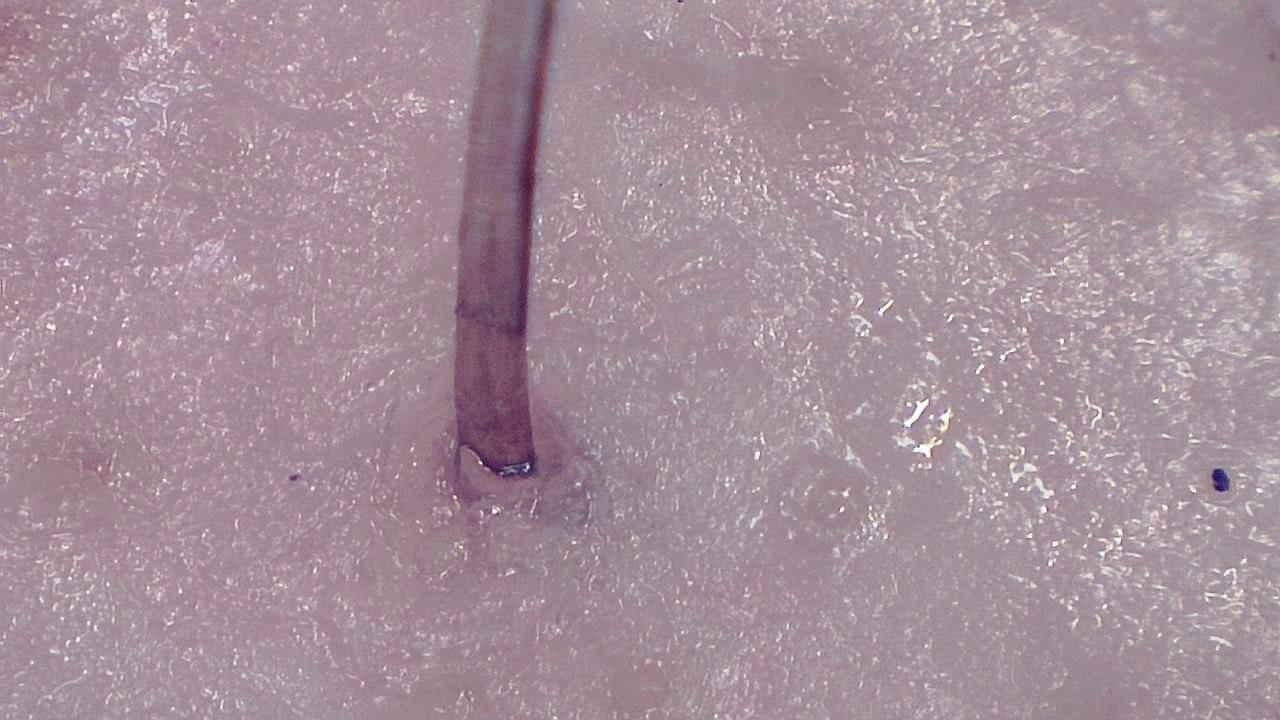

Trichoscopy is a non-invasive diagnostic technique that enables detailed evaluation of the scalp and hair shaft. Smart G-Scope provides the magnification and resolution needed to identify characteristic signs of different types of alopecia.

It is possible to visualize yellow dots, vellus hairs, follicular miniaturization, and other key dermoscopic markers used in the differential diagnosis of androgenetic alopecia, alopecia areata, and scarring alopecias.

- Visual estimation of follicular density and hair shaft thickness